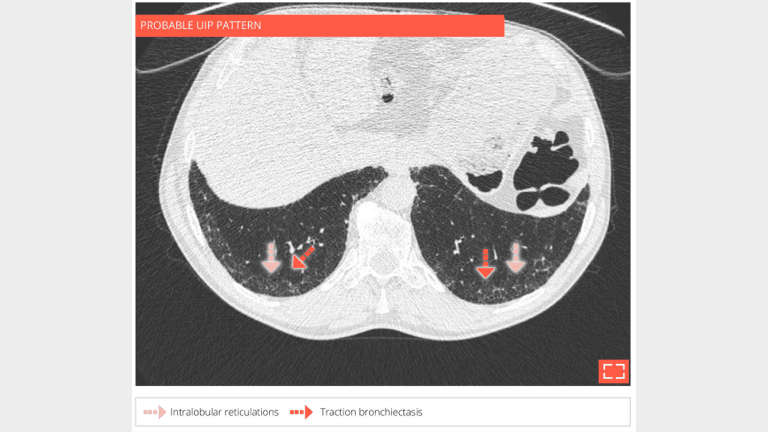

3. Intralobular reticulations

• Isolated and subtle subpleural intralobular reticulations and traction bronchiectasis of the 2 lower lobes.

• No ground-glass opacity or honeycombing.